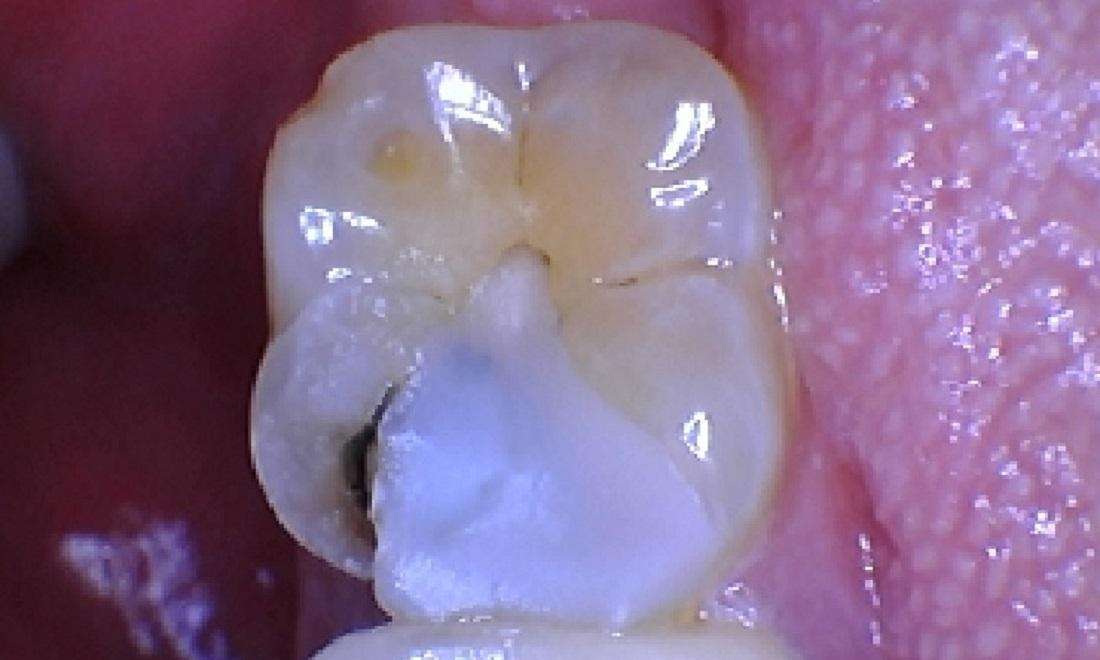

To address the issue, we carefully removed the old filling and any decayed material to ensure the tooth was clean and healthy. After the decay was removed, we applied a white filling. This type of filling is designed to bond well with the natural tooth structure, restoring the tooth’s function and blending seamlessly with the surrounding teeth.

In the after photo, the tooth appears smooth and intact, reflecting the successful restoration. The patient can now bite and chew comfortably, knowing that their tooth has been effectively repaired. This case illustrates the importance of addressing dental issues promptly to maintain oral health and preserve the integrity of the teeth.